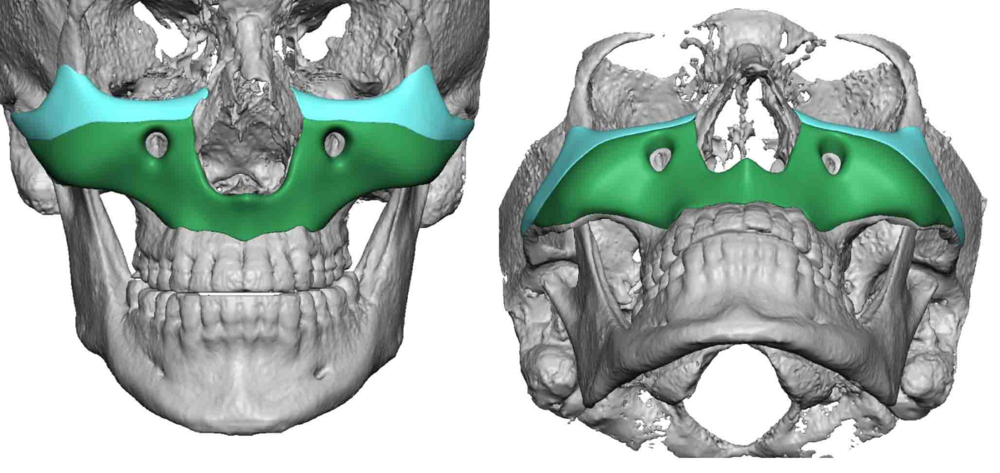

3. CUSTOM FULL MIDFACE IMPLANT https://exploreplasticsurgery.com/the-aesthetic-impact-of-a-custom-total-midface-implant/

3. CUSTOM FULL MIDFACE IMPLANT https://exploreplasticsurgery.com/the-aesthetic-impact-of-a-custom-total-midface-implant/